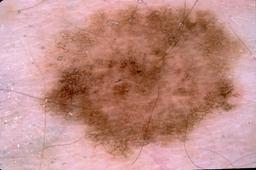

{

"age_approx": 65,

"anatom_site_general": "head/neck",

"concomitant_biopsy": true,

"dermoscopic_type": "contact non-polarized",

"diagnosis_1": "Malignant",

"diagnosis_2": "Malignant melanocytic proliferations (Melanoma)",

"diagnosis_3": "Melanoma, NOS",

"diagnosis_confirm_type": "histopathology",

"image_type": "dermoscopic",

"lesion_id": "IL_2174824",

"melanocytic": true,

"patient_id": "IP_8355925",

"sex": "male"

}